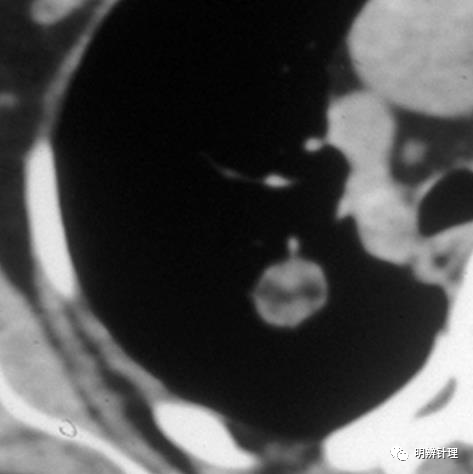

右肺上叶肺结节,实性病灶为主,中央见低密度病灶,形态不规则。酷似切开的南瓜,很有意思!

诊断结果:良性错构瘤